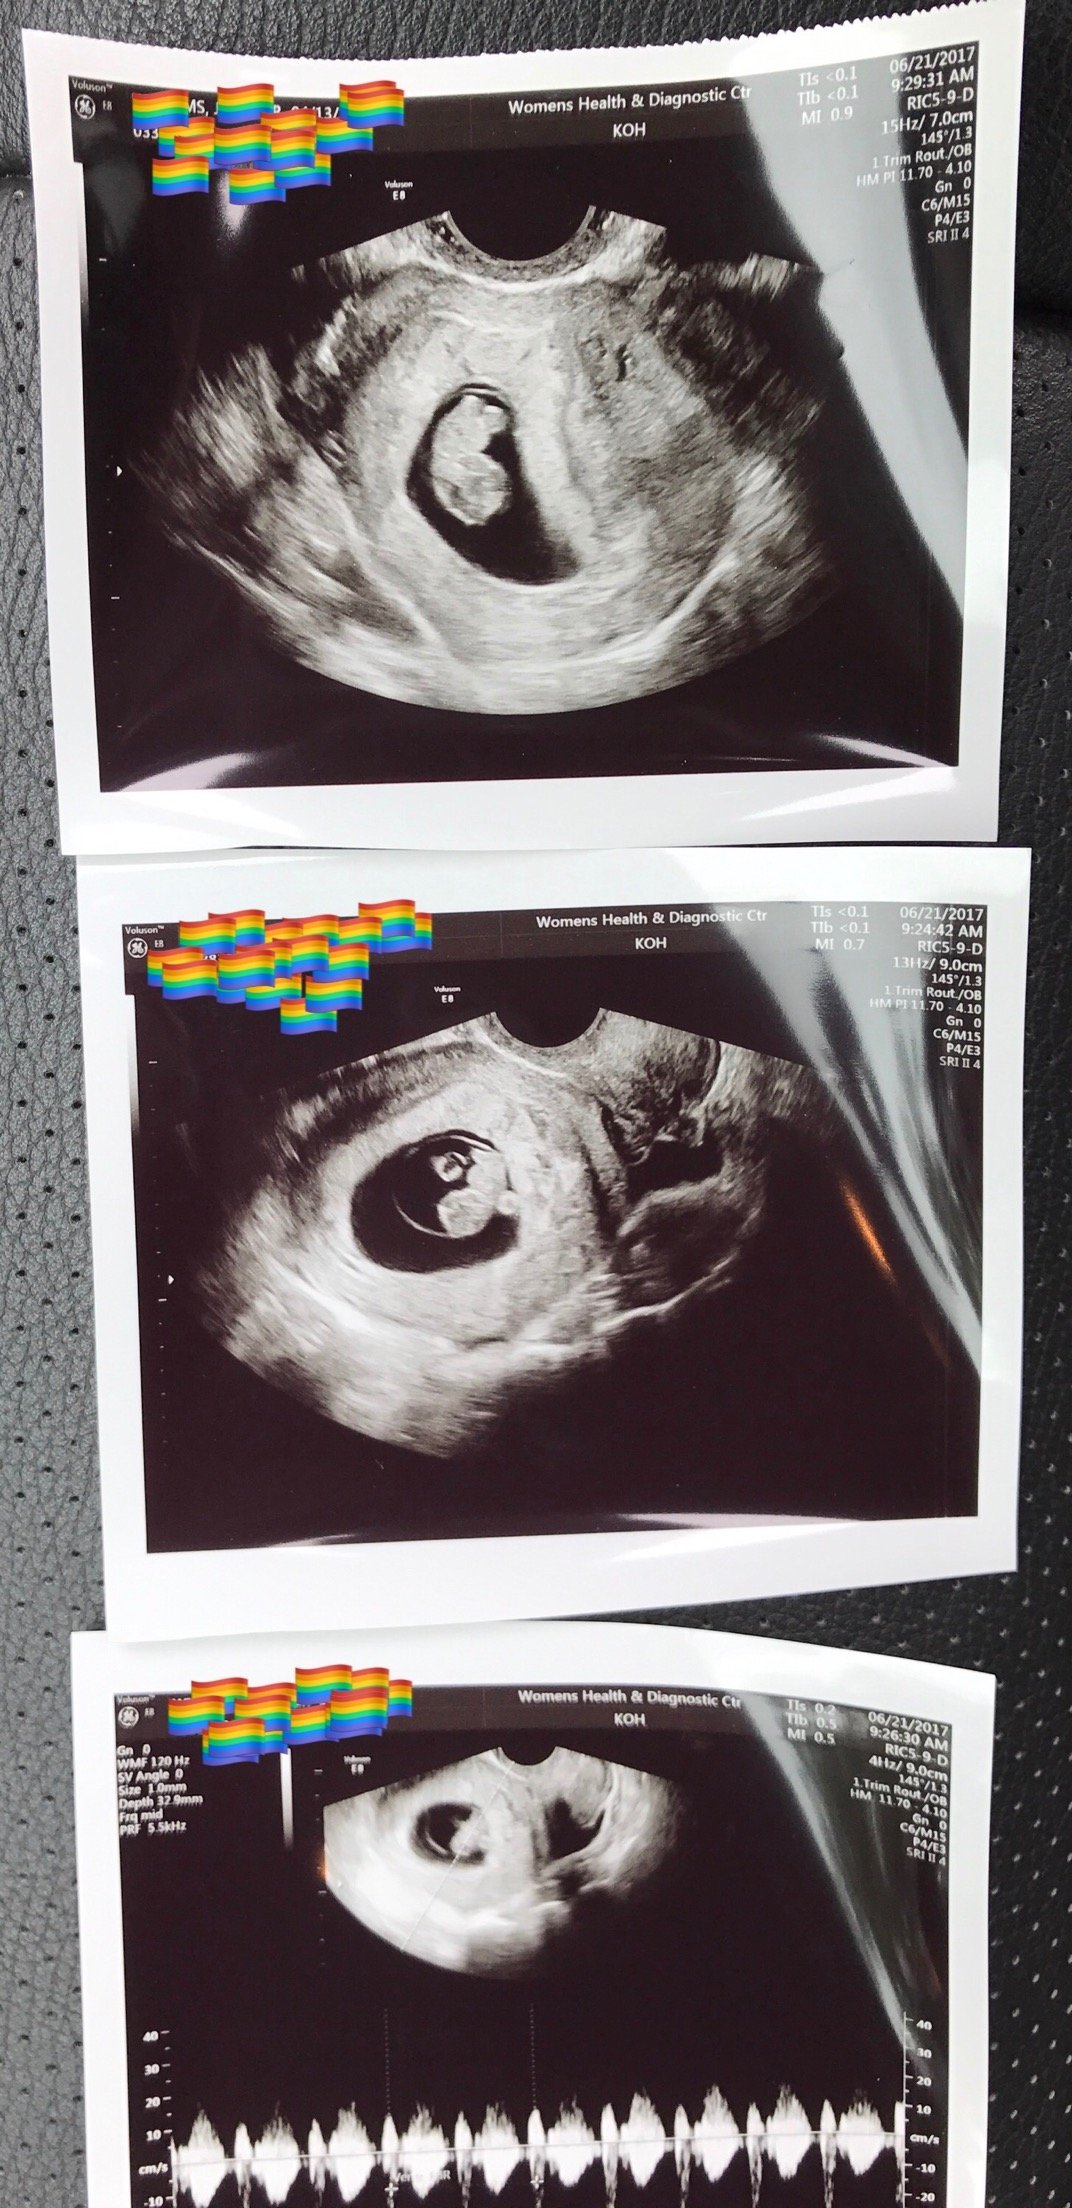

Another transvaginal ultrasound today. Everything looks great! Anyone else have an upside down babe? Last ultrasound was upside down too. By this ultrasound I'm thinking boy. Just doesn't look very girly to me!